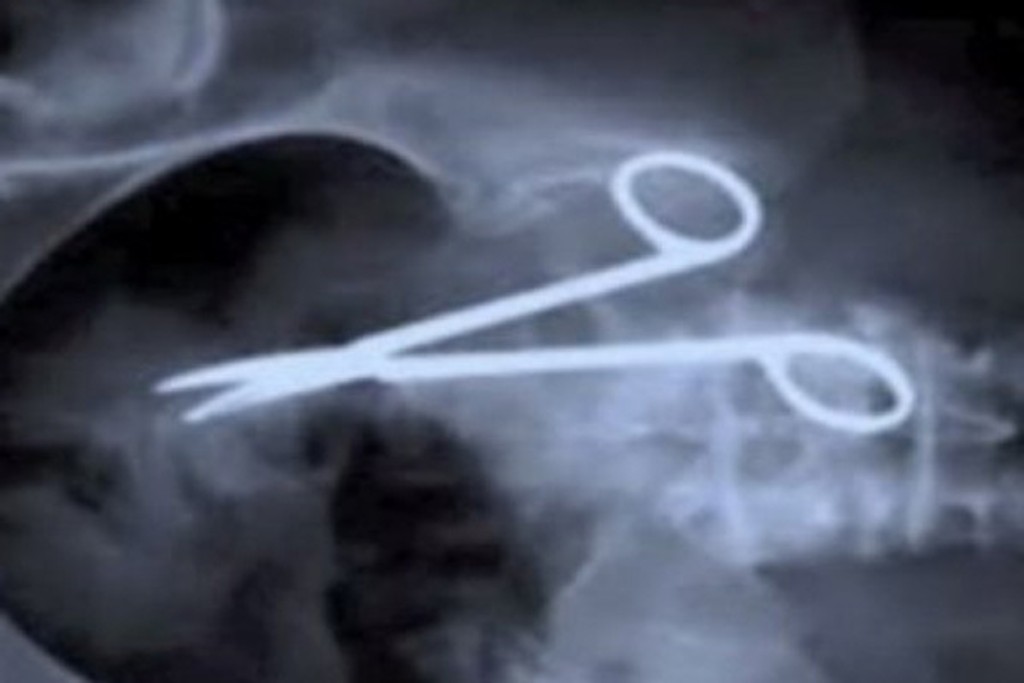

Lekári zabudli mužovi 12 centimetrov dlhú svorku v bruchu

Na monitore sa totiž objavila aj 12 centimetrov dlhá svorka, ktorú lekári zabudli v jeho útrobách pri operácii žalúdočného vredu.

Práve nástroj zvaný klieštiky, pripomínajúci nožnice, ktoré sa používajú na zastavenie krvácania, pacientovi tlačili na pľúca a stále ho nútili ku kašľu. Svorka ale hlavne dlhých deväť rokov spôsobovala Alenovi bolesti brucha, s ktorými bol dokonca niekoľkokrát hospitalizovaný. "Prvýkrát ma brucho začalo silno bolieť rok po operácii," zveril sa dnes tridsaťosemročný muž, ktorému ale lekári nevedeli pomôcť. Vyšetrovali ho totiž len s pomocou ultrazvuku a na ňom si nikto zabudnutého nástroja nevšimol.